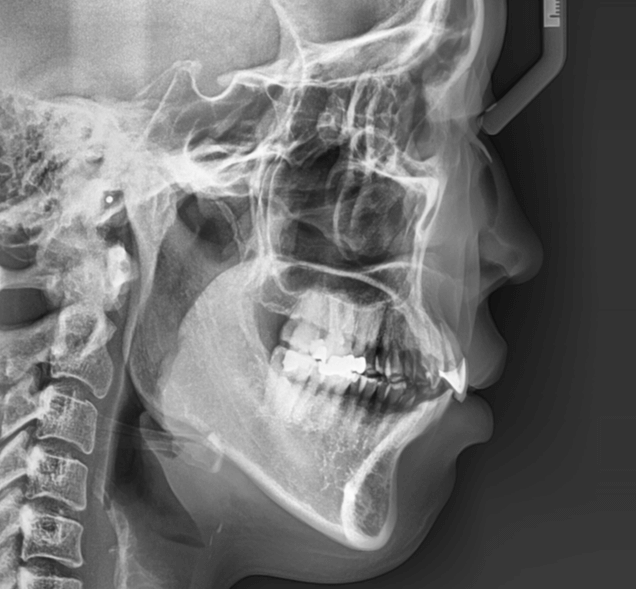

| 年齢・性別 | 22歳女性 |

|---|---|

| 主訴 | 上下顎前歯部に開咬と口元の突出感を気にされて来院された22歳女性。咬み合わせや審美的な改善を希望されていました。 |

| 治療期間・回数 | 3年9ヶ月・32回 |

| 費用 | 930,000円 |